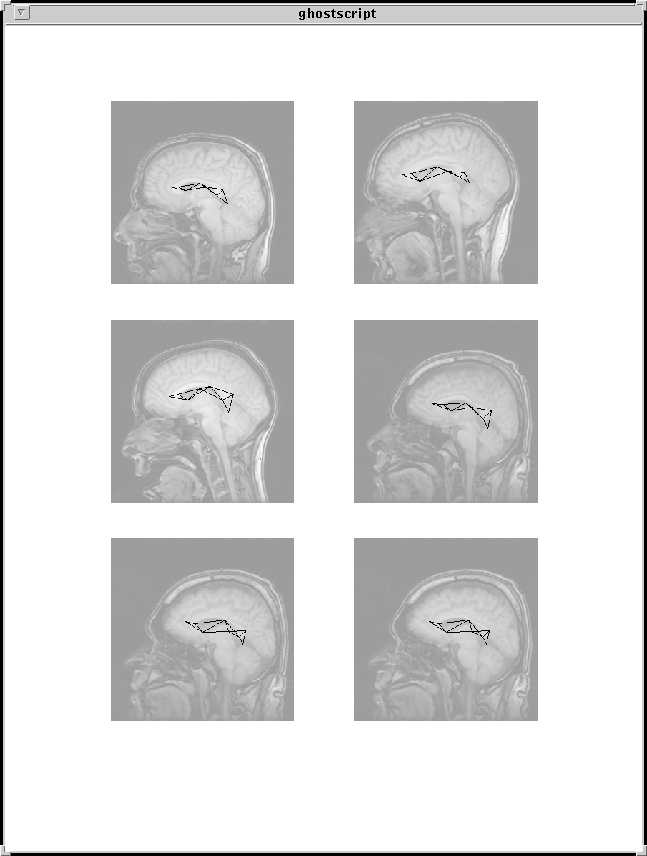

A prior distribution or cost function is defined on deformations of a graphical template of landmarks constructed from triangles, which penalizes deviations of shape of these triangles. A simple likelihood of the data given the landmark locations is formulated, using robust local operators. An image is scanned for candidates of each of the landmarks. The algorithm picks out the collection of candidates for which the penalty of the match is minimal using dynamic programming on decomposable graphs. This approach yields precise matches of landmarks of interest, and provides an object specific parameterization of shape variation. It provides a generic toolbox for modeling shape in a variety of applications. These models have been applied to hand xrays and different views of MRI brain scans and provide a means for automatic anatomy identification. See image above.

• Example: sagittal MRI brain scans

• Graphical shape templates for automatic anatomy identification with applications to MRI brain scans .